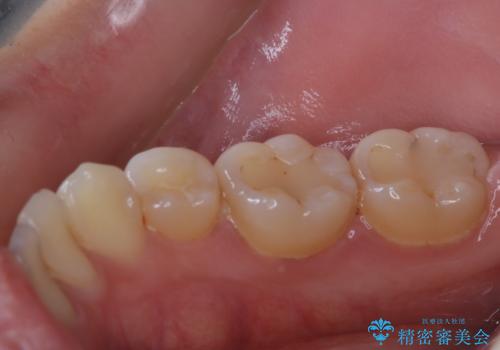

治療の前にPMTCできれいでツルツルな歯に

- 今後治療を進めていく予定で、まずはきれいにクリーニンングから行いたいとのことでした。PMTC60分コースを行いました。